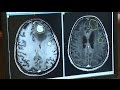

Лучевая терапия при метастазах рака молочной железы в головной мозг:

Хирургическое лечение церебральных метастазов рака почки